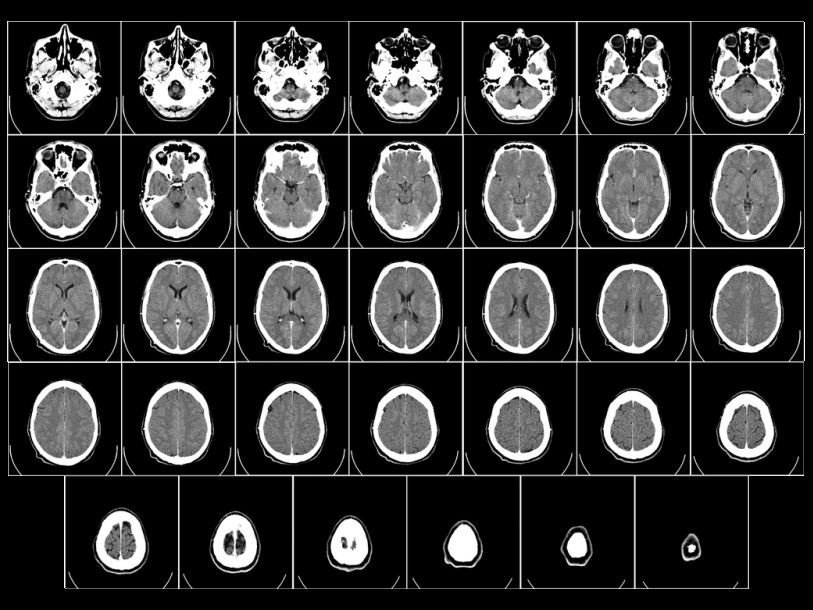

Страдающие психопатией степени люди составляют около 23% заключенных американских тюрем.В ходе исследования ученые попытались выяснить, куда у таких людей девается эмпатия. В исследовании принял участие 121 заключенный, страдающий психопатией. По результатам тестов они были поделены на группы примерно по 40 человек: с сильной, средней и слабой степенью выраженности патологии. Основной метод исследования активности мозга – это функциональная магнитно-резонансная томография (фМРТ). Когда какой-то участок мозга начинает работать активнее, кровоток в нем усиливается. Эти изменения кровотока и регистрируются с помощью фМРТ.